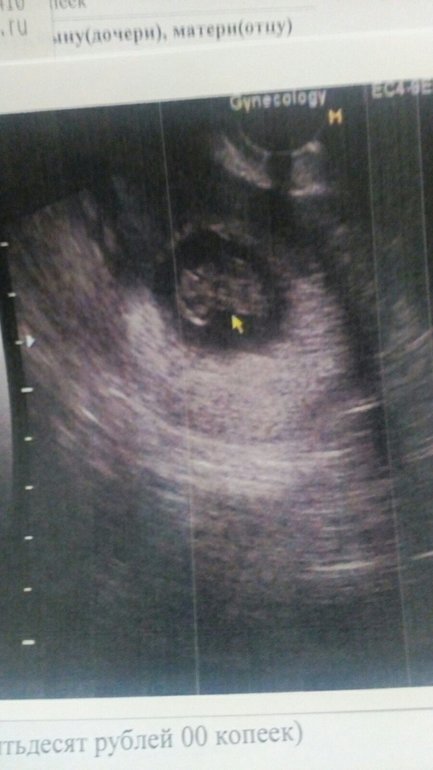

С утра сразу давай искать узи недалеко от дома - благо, нашла в соседнем квартале. Аппарат там конечно🤦🏻♀️ допотопный. Слава богу, с малышом всё хорошо😌 ктр 24мм, что соответствует 9н1д - пуля в пулю по О. Сердечко включили ❤️ на этот раз обошлось без слёз😂 179 уд/мин. Такой головастик🥰 чудо наше) доктор узи заметила даже шевелюшки, говорит «он в начале хвостиком вилял😅» поняла, что мне интересно тоже посмотреть, навела датчик и замерла😇 не заметили, естессно ничего) ну хоть попробовали😅

но мне фотку дали совсем не такую красивую - не детальную, как у вас)